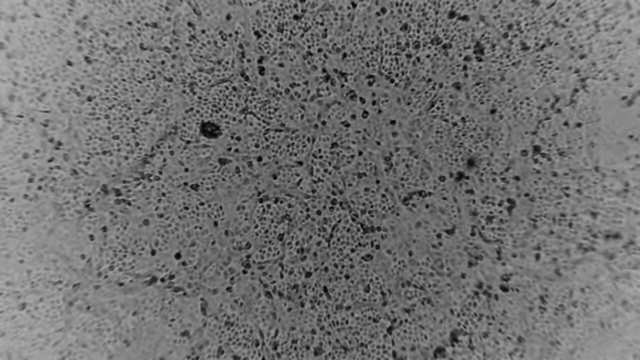

[서울=뉴시스]호주 멜버른 소재 피터 도허티 면역·감염 연구소가 29일 성명을 내고 "과학자들이 환자 샘플로부터 우한 코로나바이러스를 성공적으로 배양했다"고 밝혔다. (사진출처=피터도허티연구소 홈페이지 캡처) 2020.01.29.

호주 멜버른 소재 피터 도허티 면역·감염 연구소는 29일 성명을 내고 "과학자들이 환자 샘플로부터 우한 코로나바이러스를 성공적으로 배양했다"며 "바이러스 퇴치를 돕기 위한 중대한 정보를 제공할 것"이라고 밝혔다.